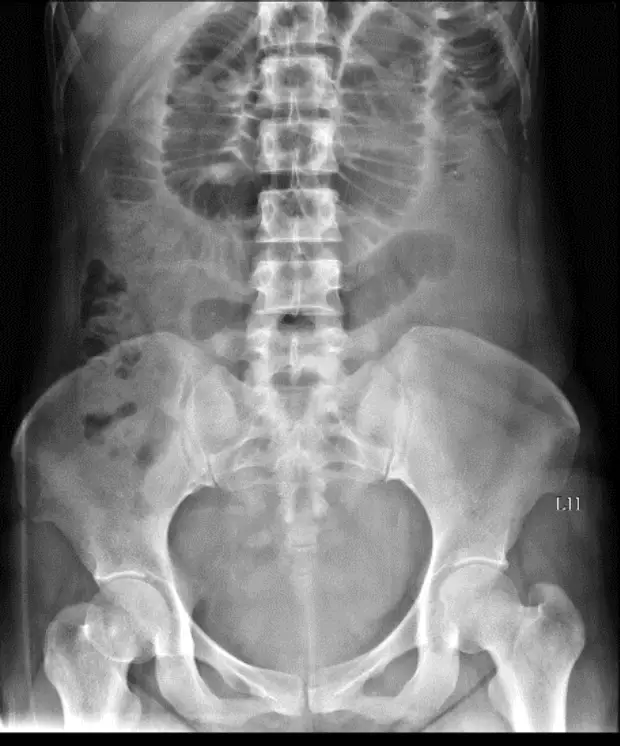

一位60歲女性因腹痛、噁心與嘔吐來急診。此病人有剖腹產與膽囊切除手術病史,其KUB如圖(二),請問最有可能的診斷為何? 圖片描述

從平躺 KUB 可見:

1. 多條位於腹腔中央的氣體擴張腸袢,最大管徑約 3–4 cm。

2. 管壁內可見連續橫跨腸腔的黏膜皺襞,呈現典型 “縱列硬幣 (stacked coins)” 及階梯樣排列。

3. 盲腸與結腸區域無明顯擴張氣體,遠端大腸疑似塌陷。

4. 未見咖啡豆或巨大單一氣腔之局部擴張。 影像特徵滿足小腸阻塞診斷要點,而多發性手術史提示以沾黏性最常見。 (radiologymasterclass.co.uk)

60 歲女性腹痛嘔吐、既往剖腹產及膽囊切除 → 高度風險腹腔沾黏。KUB 呈中央多條擴張小腸袢與 valvulae conniventes,遠端結腸無氣。影像與病史聯合判讀,最合理診斷為「沾黏性小腸阻塞」(選項 A)。